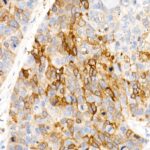

Immunohistochemistry analysis of paraffin-embedded human esophageal cancer using ALDH1A1 Rabbit mAb (A22351) at dilution of 1:400 (40x lens).Perform high pressure antigen retrieval with 10 mM citrate buffer pH 6.0 before commencing with IHC staining protocol.